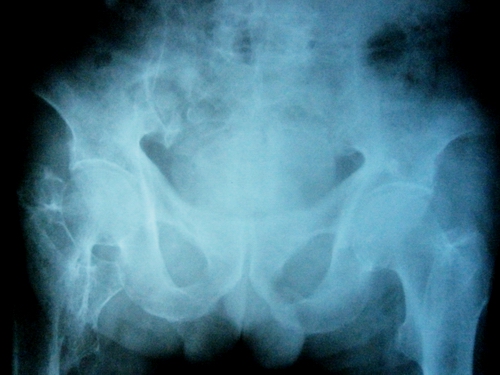

以下是引用lkc8963在2008-12-19 21:19:00的发言:[br]左?右?患侧大转子上移,股骨颈骨质浓杂,髋周见多发条片状骨化影,以小转子为著,多为陈旧性股骨颈骨折后改变并骨化性肌炎.请咨询既往史!